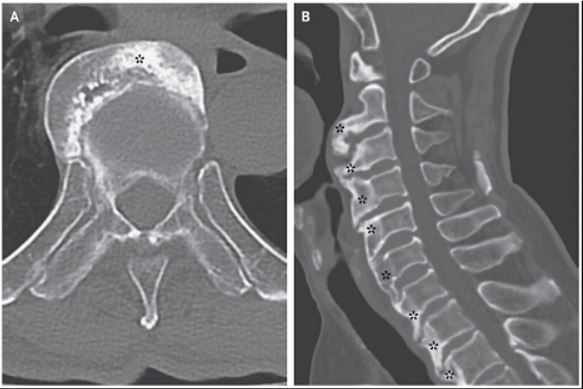

또, 추가적인 CT 촬영 검사에서 척추의 전측면이 광범위하게 골화되는 DISH의 특징적인 양상을 확인했다. 의료진은 외과적 절제를 통해 병변을 제거하는 치료를 권했으나 환자는 증상 호전을 기대하며 수술적 치료를 거부했다.